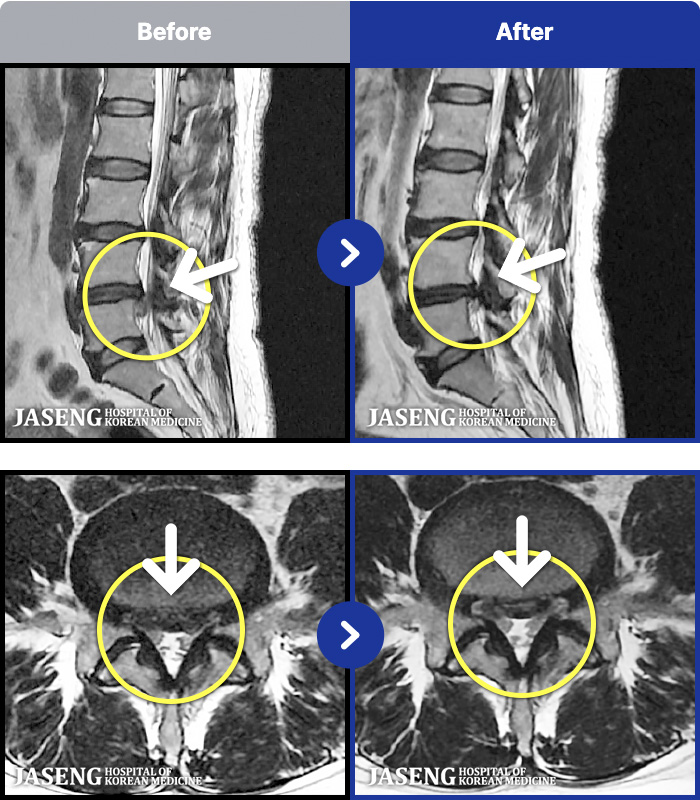

Before

After

환자에게 사전 동의를 받아 동일 조건에서 촬영되었습니다.

개인에 따라 치료 후 부작용이 발생할 수 있으니 의료진과 상담 후 치료를 진행하시기 바랍니다.

허리 골반이 아프고 오른쪽 종아리 바깥쪽으로 저리고 감각이 이상하였다.